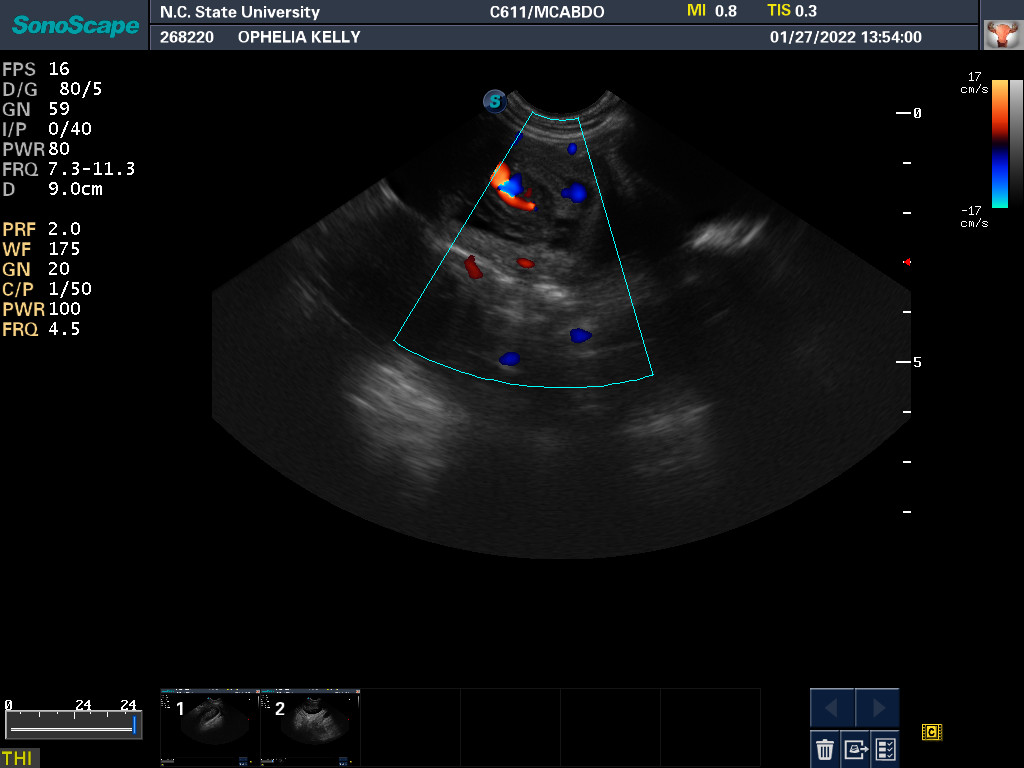

27 Jan 2022

Ultrasound today by the theriogenology (reproduction) veterinarians at NC State University showed that Ophelia is pregnant with three puppies, possibly four puppies. (It can be difficult to accurately count puppies using ultrasound.)

If all goes well, puppies are due around 24 February.